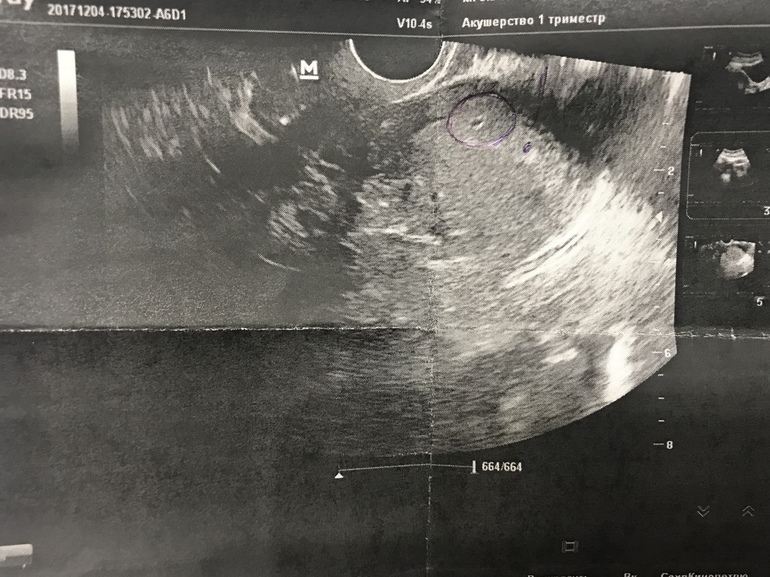

Последние месячные были 1.11. Цикл плавающий, от 28-30 дней. Овуляция была на 18-19дц. При задержке тесты ничего вразумительного мне не показывали.. только еле заметная полосочка была, больше похожая на реагент.На 35 день цикла пошла на прием к гине, смотреть меня на кресле она отказалась, если беременность, то срок слишком маленький, и смысла в таком осмотре нет..решили посмотреть на узи, что же не дает моим месячным пойти. Узи показало ПЯ 2мм, эндик пушистый и рыхлый.. беременность малого срока 2-2,5 недели от зачатия. Контроль через неделю на узи.